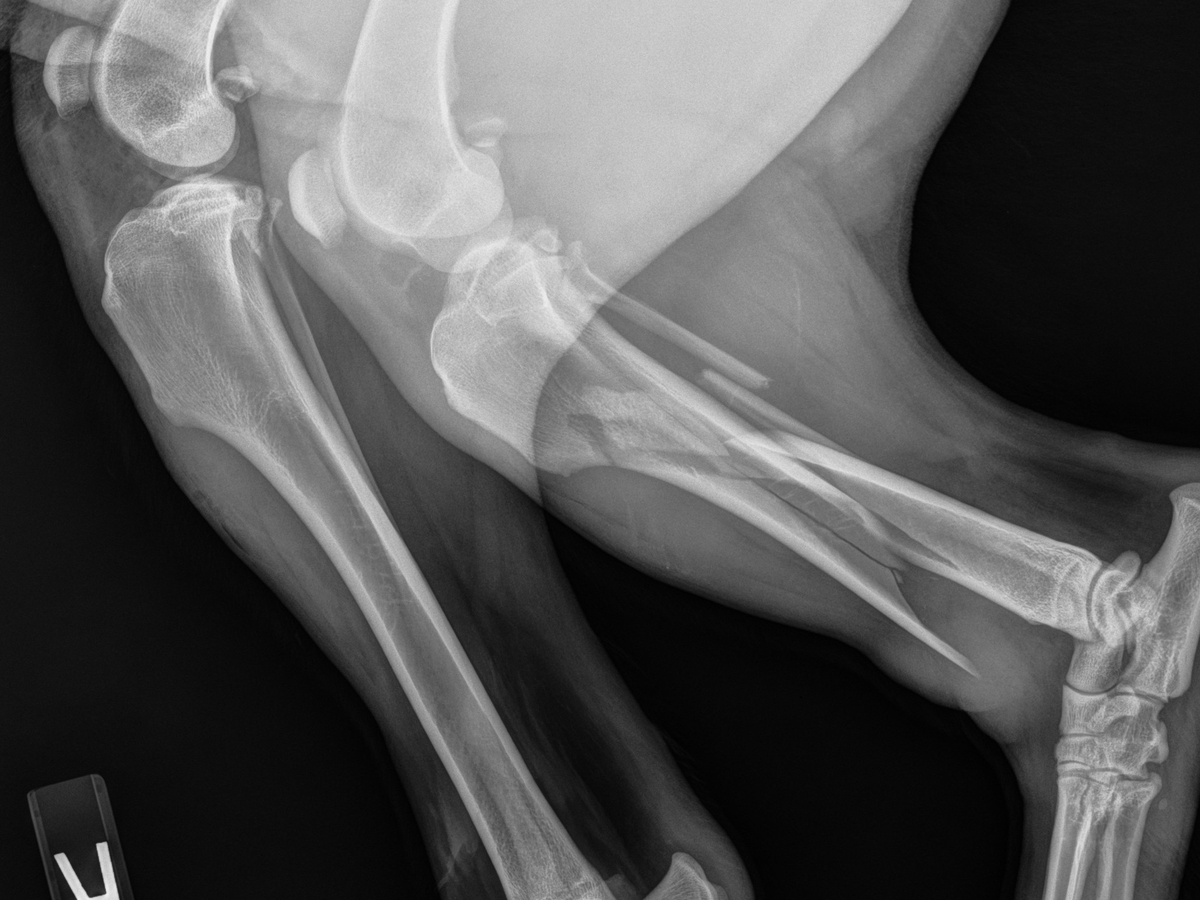

We heard the impact and found her badly injured. She was rushed to the emergency vet, where X-rays showed multiple fractures in her back leg.